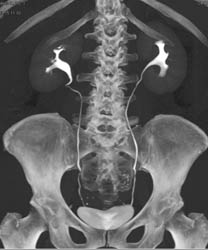

1 Cm Renal Cell Carcinoma